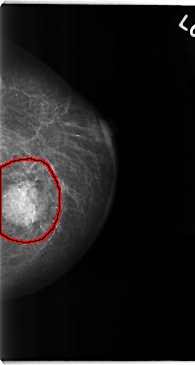

C_0111_1.LEFT_MLO

LEFT_MLO LINES 4728 PIXELS_PER_LINE 2664 BITS_PER_PIXEL 12 RESOLUTION 50 OVERLAY

FILE: C_0111_1.LEFT_MLO.OVERLAY

TOTAL_ABNORMALITIES 1

ABNORMALITY 1

LESION_TYPE MASS SHAPE LOBULATED MARGINS MICROLOBULATED

ASSESSMENT 5

SUBTLETY 5

PATHOLOGY MALIGNANT

TOTAL_OUTLINES 1

BOUNDARY